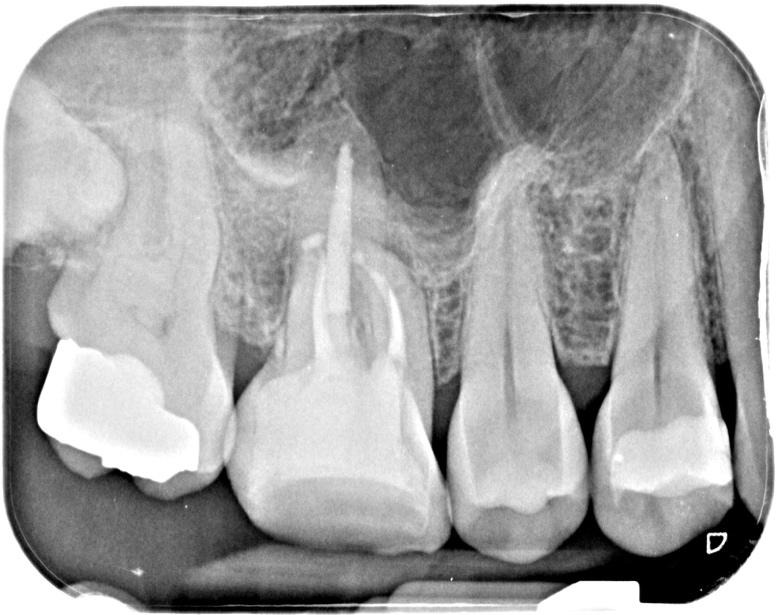

Post-op IOPA’s

As a result, the cracks were not deemed detrimental to the treatment outcome but were included in the patient’s consent and also highlighted the need for cuspal coverage straight after re-treatment in order to protect the tooth. A pre-endo build-up in 3M’s Filtek Bulk One composite helped seal these cracks beforehand. The re-root treatment was then completed using Reciproc Blue R25, VDW Rotate 2504 for the mb2 and R40 for the wider palatal canal. Following copious irrigation and lots of activation, the canals were obturated using a combination of a squirt fill technique with Totalfill BC sealer Hiflow to try and negotiate the 2-1-2 configuration apically in the mesial root and CWC in the other roots. Patency was not achieved in the palatal root. However, due to the absence of any obvious inflammatory change attached to this root on the pre-op CBCT scan it is less likely to affect the outcome of this case. This patient was then returned to their RD for cuspal coverage without delay!